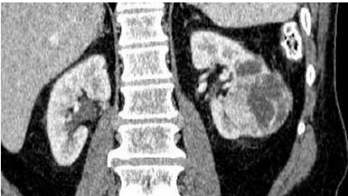

Sobre as imagens a seguir: assinale a alternativa

correspondente à classificação de Bosniak para cada

imagem.

I.

II.

III.

IV.